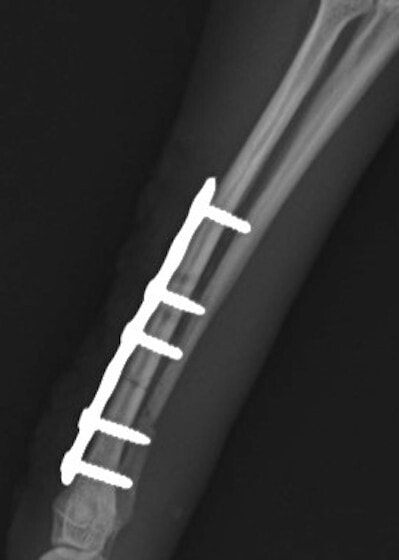

LCPは、スクリュー(ネジ)とプレート(金属の板)をロックする特殊な構造により骨折部位を固定する新しい世代のプレートシステムです。ひとつのホールでロッキングスクリューとスタンダードスクリューの使用を選択できるユニークな構造をしているため、骨折断端間の圧迫を目的とした従来型プレート固定法に加え、高い角度安定性を有するロッキングスクリューを用いた固定法の選択が可能です。従来のプレートシステムでは困難だった部分の骨折や癒合不全の症例に高い治療効果をもたらします。

Locking compression plate system の特徴

1.骨膜上の血行障害は最小限

2.高い角度安定性

3.プレート設置時の整復位喪失の防止

4.スクリューのルースニング(ゆるみ)の防止

5.コンビネーションホール

6.粗鬆骨における固定性の向上

7.1.5mmと薄いプレートのため、超小型犬にも使用しやすい

8.抜去が不要となることが多い